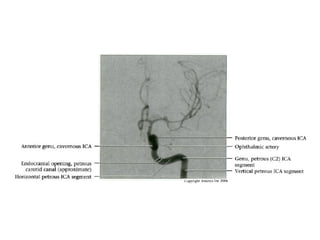

INTRACRANIAL INTERNAL

CAROTID ARTERY

Overview

• Complex course with several vertical /

horizontal segments, 3 genus (one

petrous, two cavernous)

• Six intracranial segments (Cervical lCA =

C1):

- Petrous (C2), Lacerum (C3),

Cavernous (C4), Clinoid (C5),

Ophthalmic (C6), Communicating (C7)

Overview • Complex coursewith several vertical / horizontal segments, 3 genus (one petrous, two cavernous) • Six intracranial segments (Cervical lCA = C1): - Petrous (C2), Lacerum (C3), Cavernous (C4), Clinoid (C5), Ophthalmic (C6), Communicating (C7)